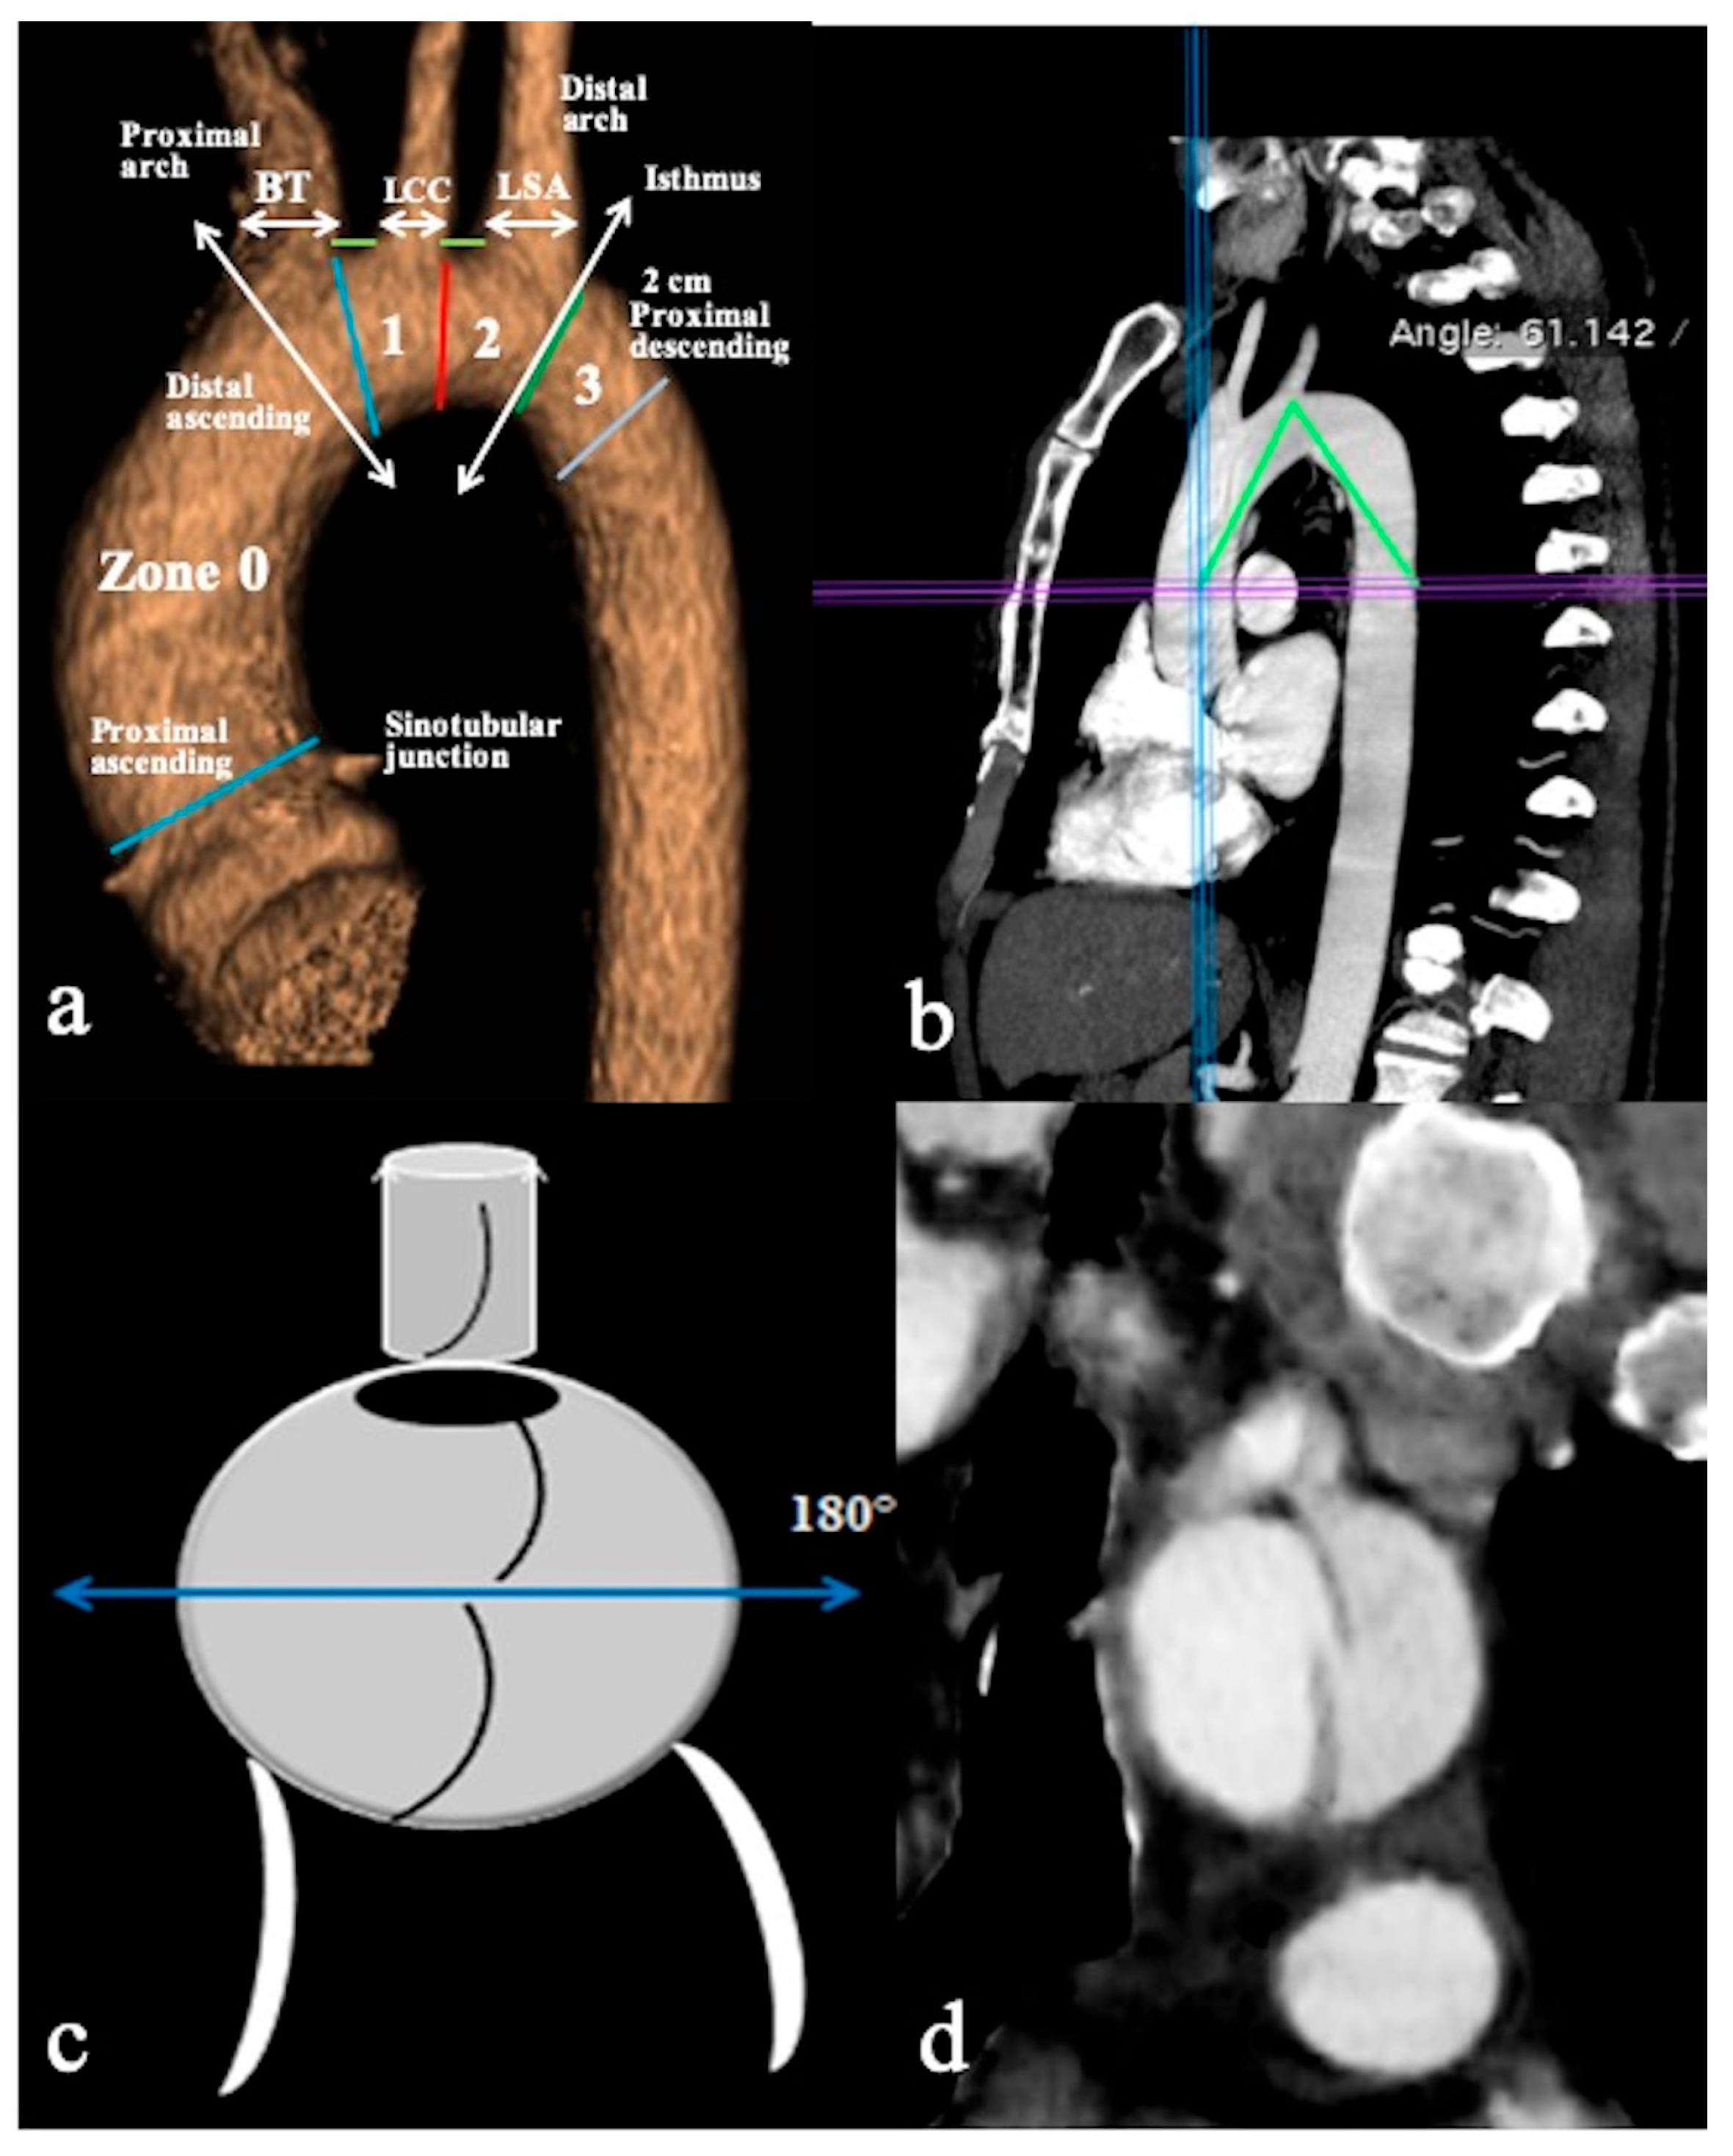

- Configuration 1 (or DTA entry): Among the cohort, 25 out of 36 patients (69.5%) presented with a type B AD or descending-entry type, with the primary entry tear distal to the left subclavian artery (zone 3). The extension of the flap occurred antegradely into the descending aorta, with or without the involvement of the abdominal aorta, and retrogradely into the aorta until the brachiocephalic trunk (BCT) (Figure 3). We describe this configuration as non-A non-B dissection with a retrograde pathway of dissection, as the entry site of the flap is in the descending aorta with retrograde arch involvement. According to Stanford classification, this configuration was present in 14% of type B AD patients. Previous studies have documented DTA entry type to be present between 10% and 25% of patients with acute type B dissection, sometimes as an intramural hematoma [33,34,35]. Patients presenting with DTA entry non-A non-B dissection demonstrated a prevalent origin of BCT and LCCA in 20% and an arch origin of the left vertebral artery in 4%. Among these cases, the distal extent of dissections was observed in various locations: the thoracic aorta in 9 patients, the abdominal aorta in 7 patients, and the pelvic circulation in 9 patients. Involvement of specific arteries was noted, including the left subclavian (n = 5), left common carotid (n = 1), or innominate (n = 1) arteries. Six of these DTA entry patients, who were initially managed with medical therapy, necessitated hybrid or surgical aortic repair within 10 days after the onset of dissection due to persistent pain (3/5), new organ malperfusion (2/5), or rapid aortic growth (1/5). Forty percent of these patients underwent treatment with optimal medical therapy and close imaging surveillance, while 60% received hybrid or open surgical therapy.

- In Configuration 2, the primary ET is situated within the aortic arch, and the dissection flap is confined solely to the arch (Arch alone). the primary ET is located in the aortic arch and the dissection flap is limited to the arch (Arch alone). This very uncommon configuration occurred in 4 (11%) patients (Figure 4) and is a very rare clinical entity. Configuration 2 is similar to the “group B” definition provided half of a century earlier by Dubost and colleagues [36], reported by Pasic in 1999 [37], and again proposed by Urbanski in 2016 [26]. An amount of 2/4 of these Arch alone patients received continued medical management with close imaging surveillance, and one- and two-year follow-up CTA examinations showed no dissection progression; 2/4 patients underwent hybrid or open surgical repair, one due to persisting pain, and the other one for cerebral malperfusion on follow-up CT.

- In Configuration 3 (Arch entry), the primary ET is situated within the aortic arch, and the flap extends into the DTA without affecting the ascending aorta [38]. This Configuration 3 occurred in 7 (19%) patients (Figure 5a,b). This AD configuration was already described as proximal type B dissection according to 2010 AHA guidelines [7] and recently reported as arch B group AD from IRAD [38] and as non-A non-B acute AD with entry tear in the aortic arch [39,40]. In this configuration, the ET was often located in the greater curvature of the arch (4/6), while in one case (1/7) its location was not clearly identified. In total, 4/7 of these patients underwent hybrid and 2/7 surgical therapy.